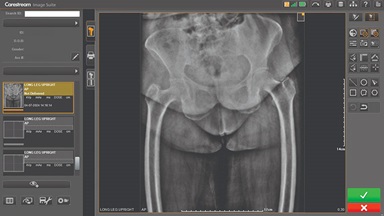

CARESTREAM Image Suite V4 MR11 has set a new standard for workflow efficiency, offering a robust set of features and functionalities to enhance clinical confidence in healthcare professionals. Using an auto-generated companion image from a single exposure, leverage a range of image processing options to increase diagnostic accuracy and enhance patient care.

Upgrading your imaging system to a solution designed for outstanding image quality is no longer out of reach — it's now easier, more affordable, and more effective than ever before.

Our Carestream Focus HD 35/43 Retrofit Detectors, powered by Image Suite Software, are an ideal solution to step up to full digital X-ray for customers who simply cannot compromise on image quality. It seamlessly integrates into existing setups, bringing the power of full digital X-ray with minimal disruption and maximum clarity, along with the following benefits: